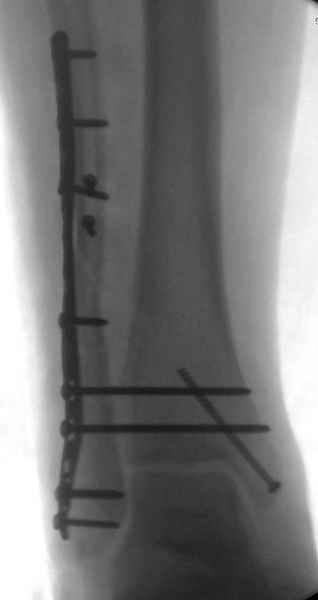

>На сделанных у нас снимках видно, что не все благополучно...

Неравномерность суставной щели может быть связана с разрывом глубокой порции дельтовидной связки и ротацией м/берцовой кости за счет поврежденных структур синдесмоза(репозиция ее на уровне перелома как-будто удовлетворительная).

Мы бы, сблизив берцовые кости чрескожно наложенным репозиционным зажимом, провели позиционный межберцовый винт чуть ниже пластинки в положениий максимального тального сгибания стопы и ... на следующий день разрешили бы полностью наступать без гипса, брейса и т.п., но в обуви с небольшим каблуком 2-3 см и супинатором. Через месяц-полтора -винт удалить (если конечно не сломается).

По моему мнению,ассиметрия суставной щели обусловлена импрессией медиальной части суставной поверхности б/б кости. Да, позиционный винт здесь не лишен, но через 4 недели целесообразность его проведения сомнительна, брейс, ограничение осевой нагрузки достаточно.Есть еще деонтологические аспекты повторной операции, не все так плохо выполнено предыдущим доктором!

Выполнено действительно неплохо, только позиционный винт забыли провести.

Вот и я тоже так думаю.

Перелом типа Вебер С с эверсионным механизмом травмы всегда сопровождается повреждением дистального межберцового синдезмоза, поэтому вместе с фиксацией переломов лодыжек( малоберцовой кости) автоматом выполняется фиксация синдесмоза винтом, который обычно удаляется через 8 недель -

перед началом полной нагрузки на ногу.

Здесь похожий случай трехнедельной давности, перелом почти сросся и была укорочена малоберцовая, на операции длину малоберцовой смогли восстановить только после того, когда проксимальнее пластины ввели шуруп и использовали его как толкатель, с помощбю дистракционого инструмента (lamina spreader).

Меньше всего волнует положение медиальной лодыжки - в любое время можно провести остео или реостеосинтез, при несращении можно просто резецировать без ущерба для движений в голеностопе. Здесь обошлись фиксацией одним 4 мм канюлированным шурупом.